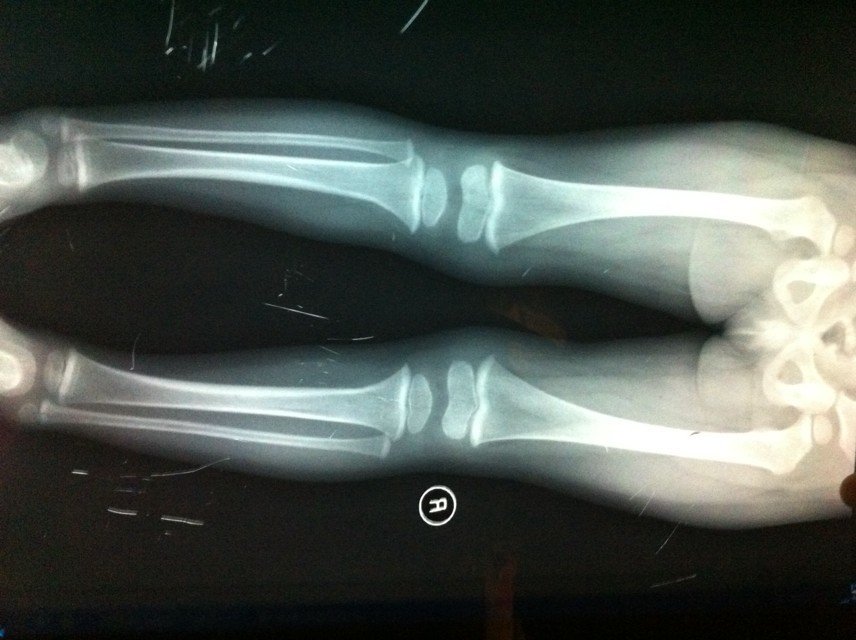

我家宝宝走路有点瘸,以前好好的,以为小儿麻痹症,也没有摔倒,到医院查不出来什么,医生说是上火 拍X光片也查不出来什么,没有异常。不知道说什么原因,前面15天还发了次烧。 求讲解。 点击展开 匿名用户 2014-06-08 12:08 为您推荐: 其他回答 指导意见: 现在的情况可以查下血来确定发烧的原因为好的,再治疗,增加营养,增强体质为好的有利于身体健康的。 操朋兴_Tkly 2014-06-09 13:04 相关问题 宝宝腿不疼但是走路瘸骨骼发育都正常会是小儿麻痹症吗 小儿麻痹症20多年了能走路还能针灸治疗吗,有好处吧 原来的一个故事,说的是一个人从小患有小儿麻痹症,不能走路,但是后来他却跑出了世界上最好的成绩,是一